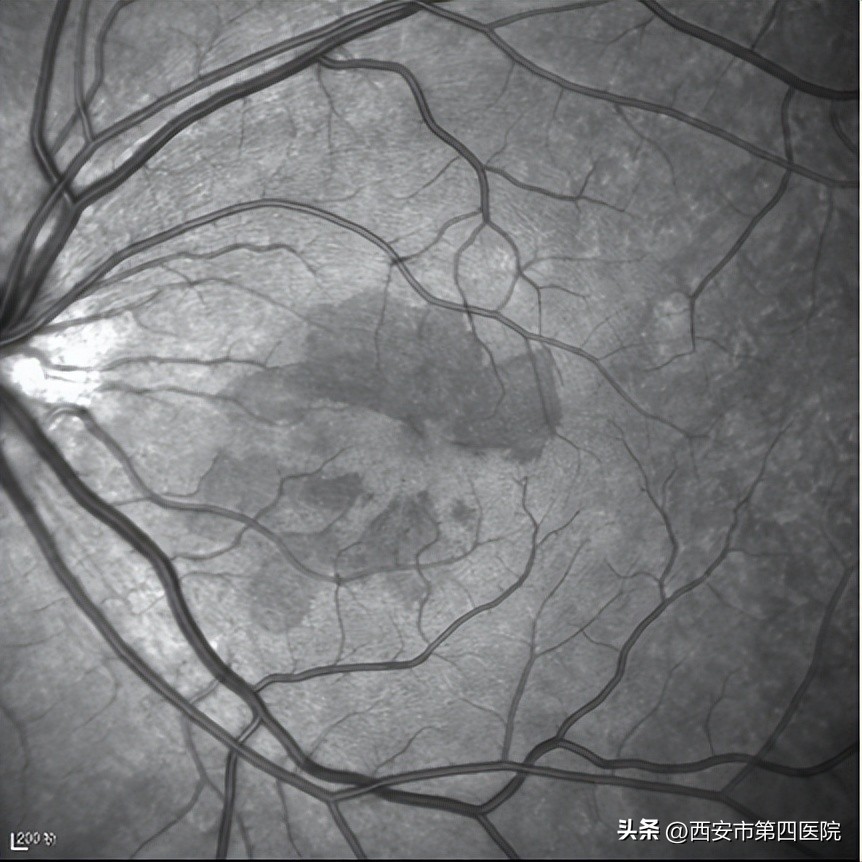

王海燕主任立即安排患者做了检查,患者右眼视力0.6,左眼视力1.0,眼压正常,眼底检查和红外(IR)成像发现双眼眼底有“花瓣状”暗红色病灶,尖端指向中心凹

双眼眼底彩照所示: 黄斑区深褐色改变;

双眼红外(IR)成像:所示黄斑区可见“花瓣状”低反射信号,尖端指向中心凹)